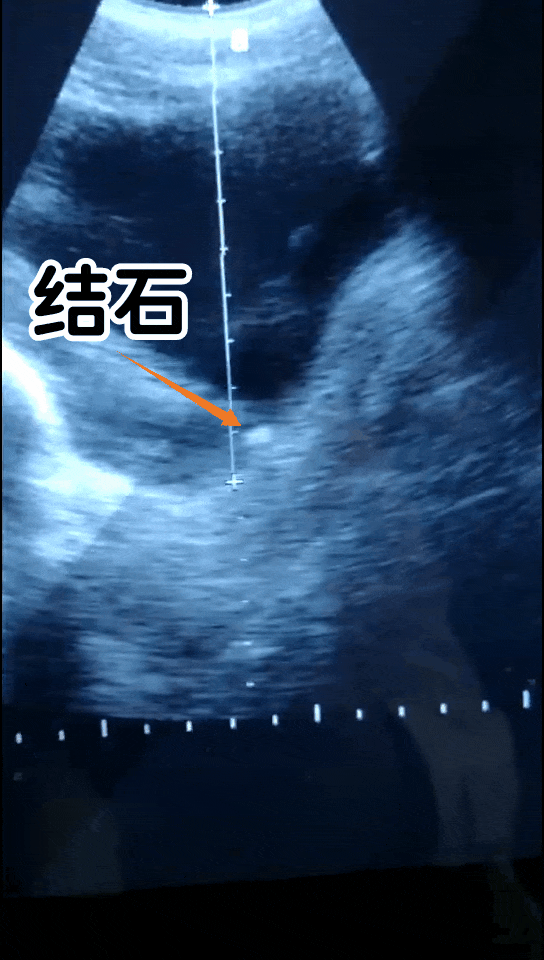

1. 肾结石

夏季炎热、水分蒸发快,如再加上不合理的生活饮食习惯如喝水少、久坐憋尿、爱喝啤酒等,就会导致尿液中的钙质沉淀、增加肾结石的几率。典型症状有疼痛、血尿、排石等。

肾结石如何治疗?

①药物治疗:适用于<6-8mm的结石,而且没有比较严重的症状,比如血尿、高热等。

②手术治疗:适用于无法排出的结石,建议到医院进行手术治疗。

③冲击波碎石治疗:适用于<2cm的肾结石。

(碎石瞬间)